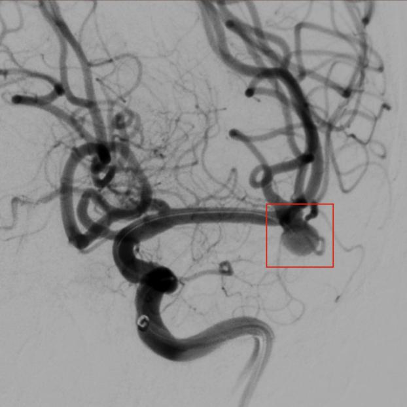

栓塞前的脑血管分叉处动脉瘤。